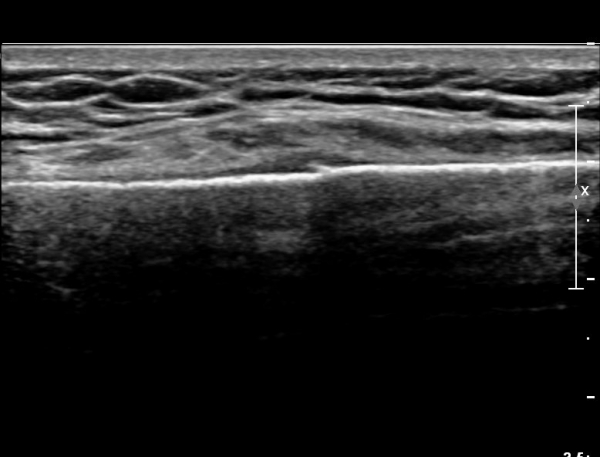

Äá¾Ë»À Á¾´Ü¸é°Ë»ç¿¡¼­ Äá¾Ë »À ±ÙÀ§ºÎÀÇ ÇÇÁú°ñ °ß¿­ÀÌ °üÂûµÊ(»çÁö 4).